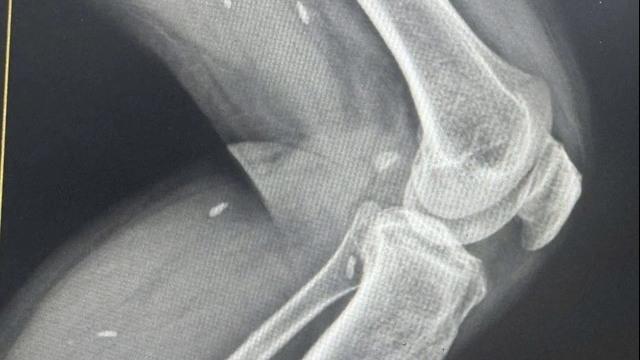

| Hình ảnh các các sỹ cấp cứu bệnh nhân tại Bệnh viện Đa khoa tỉnh Thanh Hóa. |